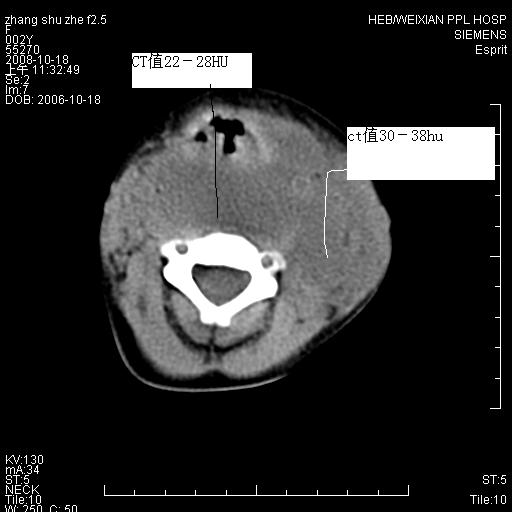

以下是引用dyqct在2009-2-10 21:04:00的发言:[br]年龄?性别?有发烧吗?[br]鼻咽部、口咽部、喉咽部及颈椎前间隙广泛肿厚,明显占位效应并致相应组织变形。ct值22-28hu。[br]考虑:1、颈前脓肿可能性大;[br] 2、建议增强或治疗后复查。

以下是引用jiangjing在2009-2-11 11:37:00的发言:[br]急性病程,鼻咽部、口咽部、喉咽部及颈椎前间隙广泛肿厚,明显占位效应并致相应组织变形.考虑颈部感染性病变(脓肿?);建议行进一步检查。